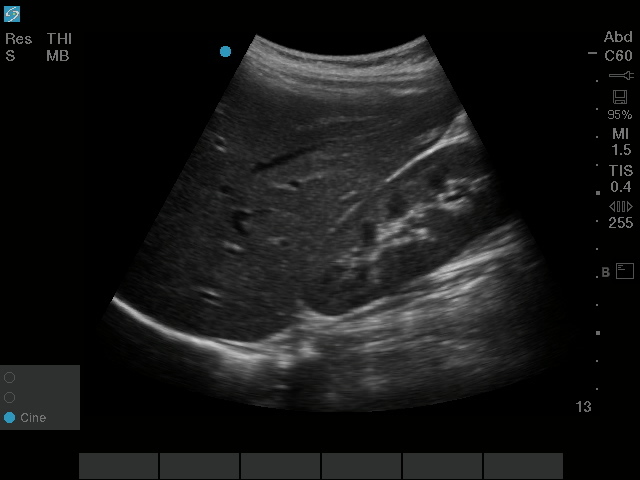

Bild des rechten oberen Quadranten (ROQ) mit dem rC60xi